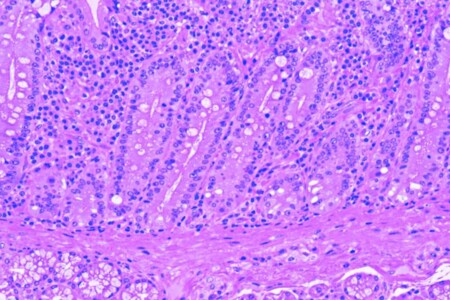

Střevní polypy jsou útvary, které vyrůstají z povrchu střevní sliznice a představují významný rizikový faktor pro vznik kolorektálního karcinomu, tedy rakoviny tlustého střeva a konečníku. Včasné odhalení a odstranění polypů tak může zabránit rozvoji tohoto zhoubného nemocnění. Proto je nezbytná prevence a informovanost široké veřejnosti.

Kolonoskopie je endoskopické vyšetření tlustého střeva. Při kolonoskopii se do střeva zavádí flexibilní hadice, na jejímž koci je kamera přenášející obraz na monitor, kde jej sleduje lékař, který kolonoskopii provádí. Kolonoskopie slouží k odhalování nemocí tlustého střeva a často také k jejich léčbě, stejně tak jako k odebírání vzorků tkáně ze střeva.